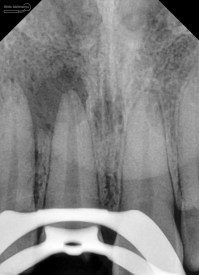

dan ini hasil ronsen final…

Foto radiografis akhir

Terlihat padat dan hermetis dari ujung sampai ke crown….